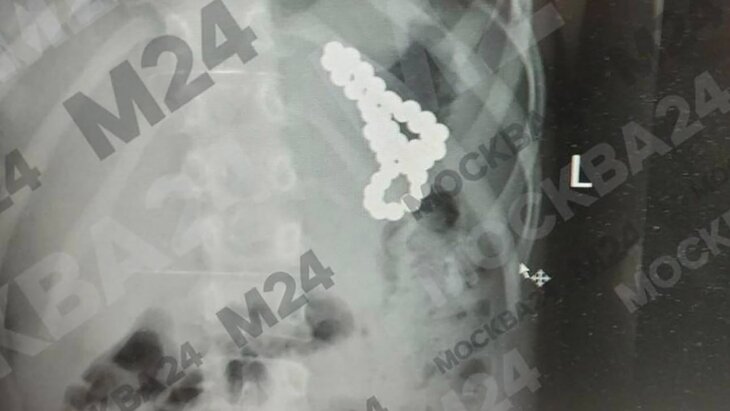

Московские хирурги спасли школьницу, проглотившую 46 магнитных шариков

18 февраля 2025

Московские врачи спасли младенца, проглотившего ключ-скрепку от сим-карты